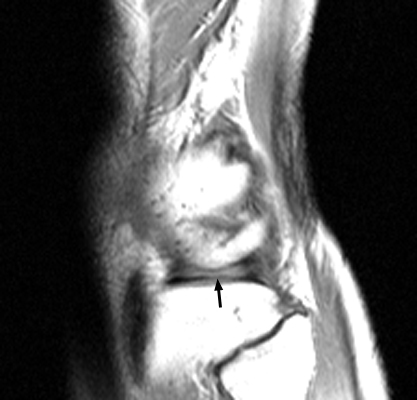

Diagnosis:Bucket-handle tear of the menisci Discussion:Multiple sagittal T1 weighted images which reveal loss of the normal bow-tie appearance of the meniscus. The "absent bow tie sign" is another good sign of a bucket handle tear of the meniscus. The absence of the normal bow-tie is secondary to the displaced fragment which makes up the "handle" of the bucket. Requirement for the absent bow tie sign mandates that the normal requirement of at least two adjacent sagittal images with a normal meniscal body segment appearance is not present. References: